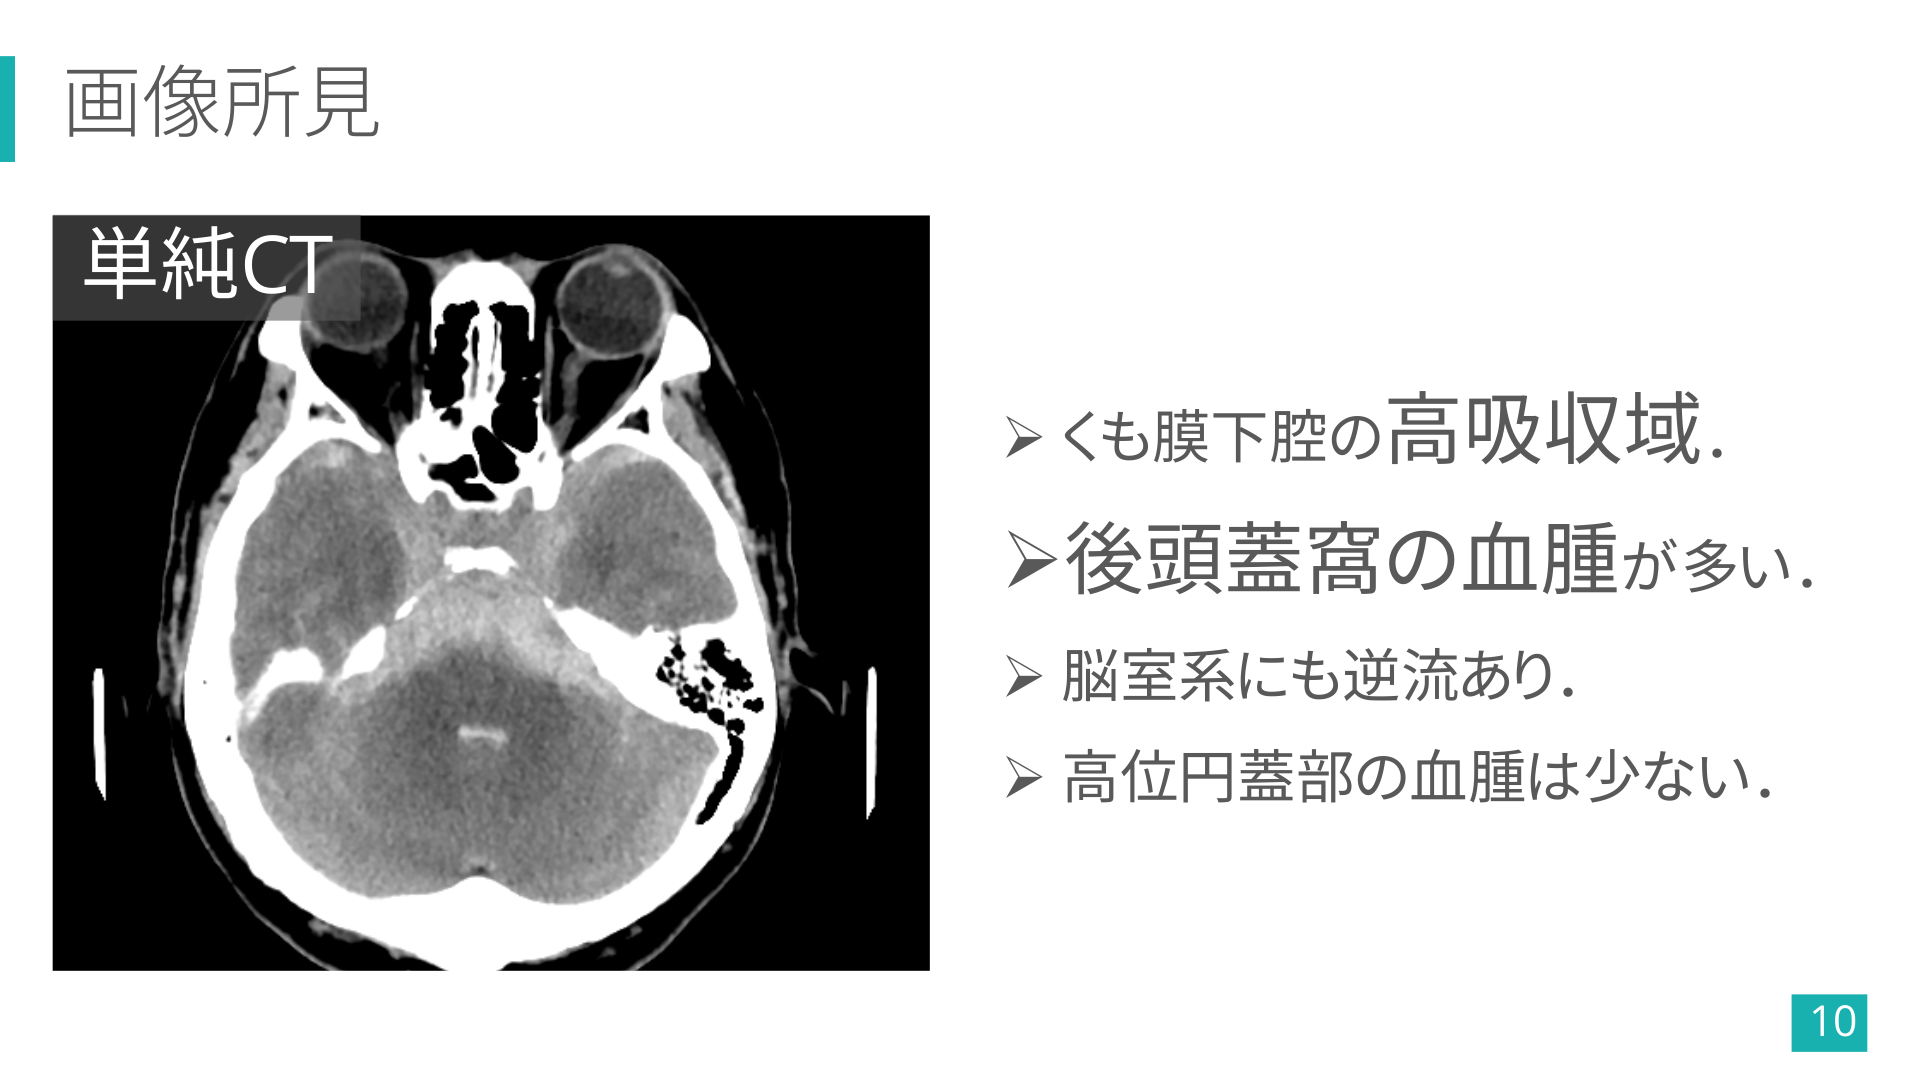

画像所見 単純CT Ø くも膜下腔の高吸収域. Ø後頭蓋窩の血腫が多い. Ø 脳室系にも逆流あり. Ø 高位円蓋部の血腫は少ない. 10